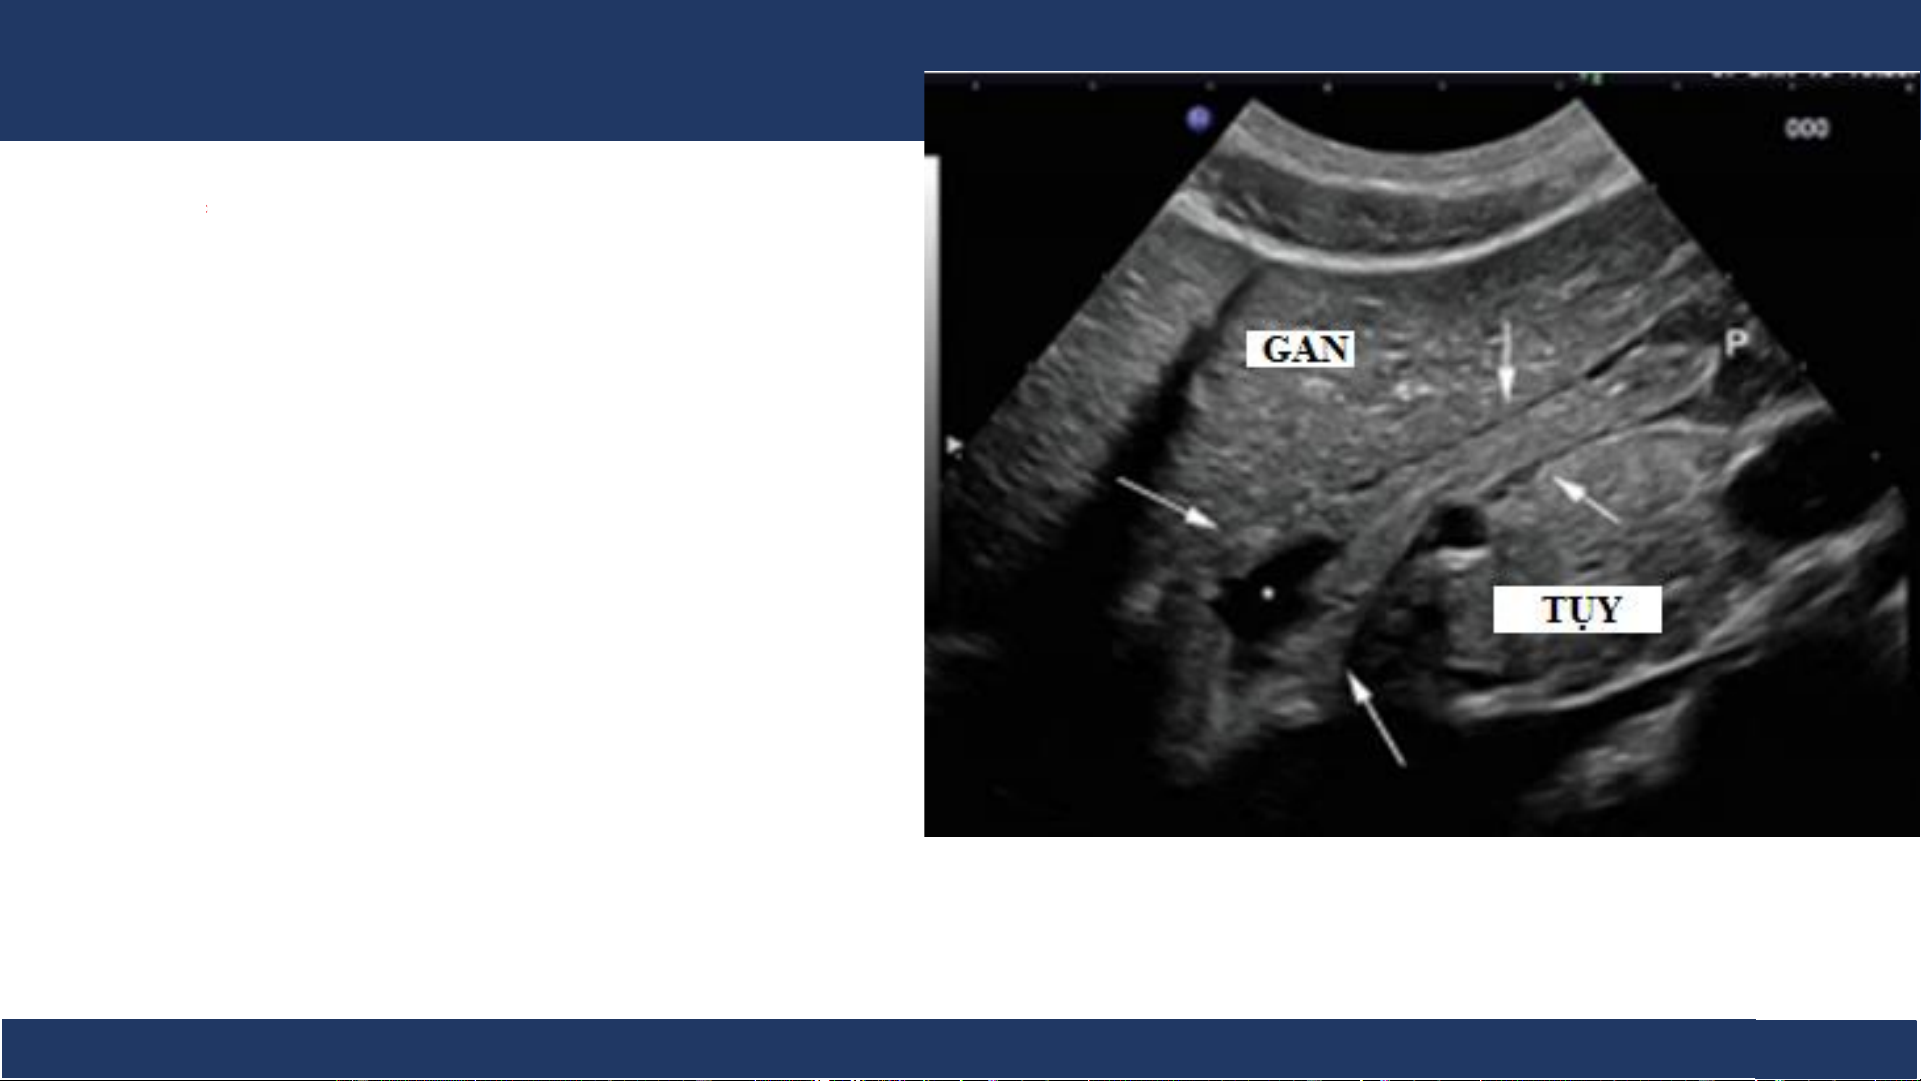

hình ảnh, ĐHYD TPHCM 10 SA: Dạ dày .

Trên siêu âm có thể khó thấy dạ dày nếu chứa nhiều hơi

Độ dày bình thường của thành dạ dày: <5-6mm. Dạ dày (mũi tên) Bệnh v B iệ ộ môn n Nh Chẩ i Đồng n đoán 1

hình ảnh, ĐHYD TPHCM 11 SA: Dạ dày

Phình vị và thân vị thường có .

dạng túi dịch lớn, dễ nhầm lẫn ổ

tụ dịch dưới hoành trái. Phân biệt

= luồng dịch chuyển động khi nuốt.

Phần ngang và hang vị thường xẹp khi nằm ngửa

Môn vị và hành tá tràng: dễ thấy

khi đầy dịch và nằm nghiêng phải, có nhu động.

Dạ dày (phình vị và thân vị) Bệnh v B iệ ộ môn n Nh Chẩ i Đồng n đoán 1